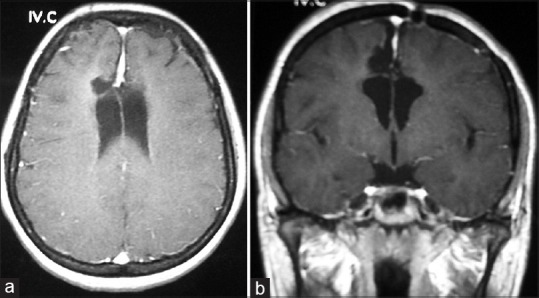

A 21-year-old female patient who had been suffering from a headache for about 2 years applied to an ophthalmologist with the loss of sight for the last 6 weeks. On her cranial magnetic resonance imaging (MRI), an intracranial tumor had been diagnosed and was referred to the neurosurgery clinic. Her cranial MRI showed a mass measuring approximately 45 mm *70 mm at the vertex level localized within the interhemispheric fissure, T1-weighted gadolinium-enhanced MRI images showed a characteristic dural tail sign, containing perifocal edema and compressing corpus callosum and the lateral ventricles [Figure 1]. There was no history of seizures and no significant neurological examination finding in the patient except a decrease in visual acuity. Due to the fact that the patient was in her reproductive age a β–human chorionic gonadotropin analysis was ordered and found to be high (2598 mIU/ml N: 0–5,3). Being G2P1Y1 a pregnancy was possible thus she was consulted to the obstetrics and gynecology clinic. She was late to her last menstruation cycle for 5 weeks and 6 days, and her obstetric ultrasonography revealed a fundal localized gestational sac measuring approximately 6 * 8mm corresponding to a gestational age of 5 weeks. She was then evaluated multidisciplinary with a neurosurgeon, ophthalmologist, obstetrician, and anesthesiologist. With the consent of the family, her pregnancy was terminated, and the patient was transferred to our clinic.

Figure 1.

Preoperative T1-weighted gadolinium enhanced magnetic resonance imaging, axial view (a) and coronal view (b) showing a large interhemispheric meningioma compressing the lateral ventricles